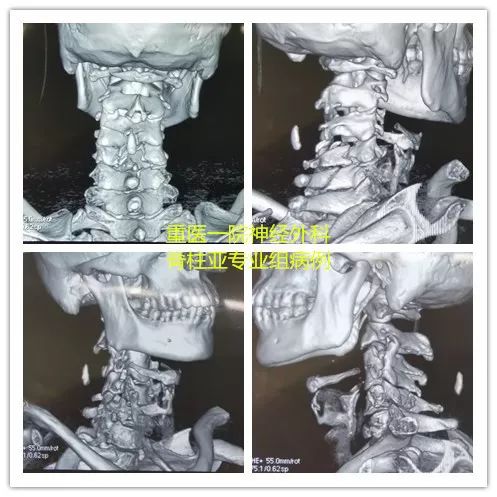

术前影像

CT提示:患者颈6椎体暴裂样骨折,骨折片突入椎管,致椎管明显狭窄;合并颈5棘突骨折,颈5、6椎弓根骨折。

AO分型为C5-C6:C(C6-A4;F1,F1;N4;M1)。